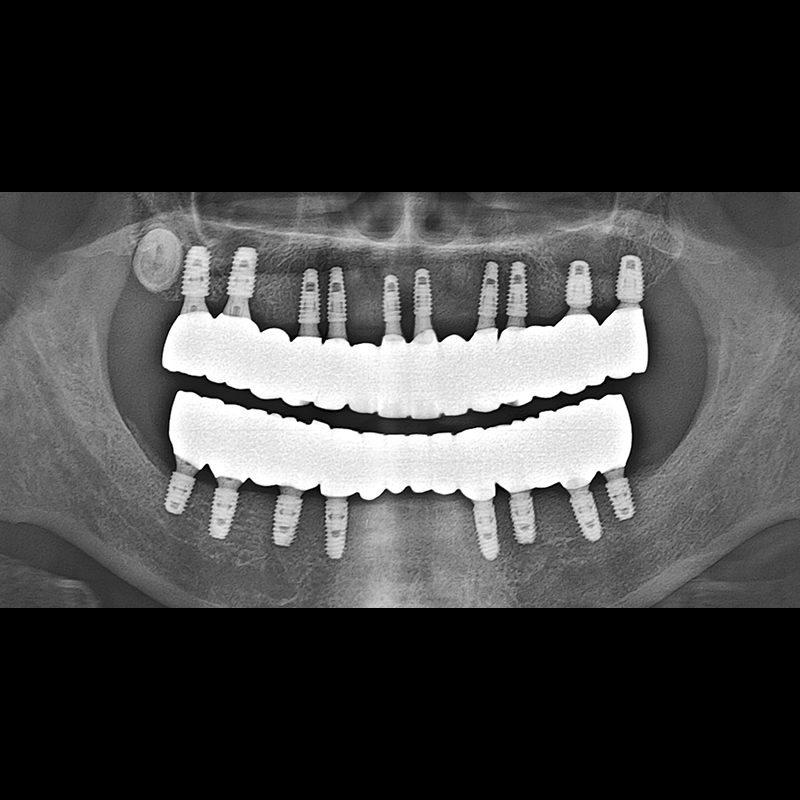

BEFORE AFTER

インプラント手術事例 2025.05.30

欠損した歯の部分と、生かしにくい歯の位置にインプラントを植立しました。